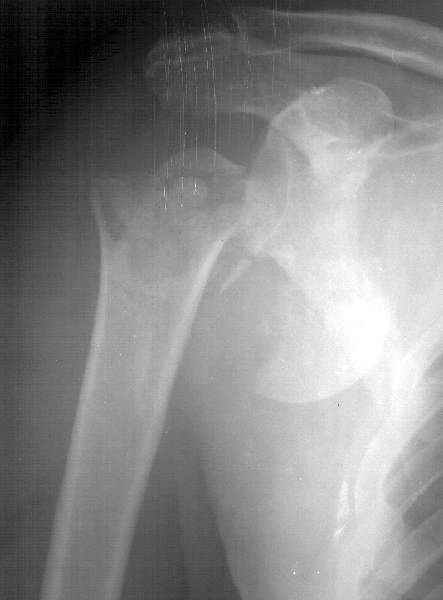

Перелом и вывих плеча

Мужчина 61 г., получил 6.04.02 в ДТП (лобовое столкновение) вывих плеча с переломом большого бугорка и не бросающимся в глаза переломом анатомической шейки (см здесь ). В ЦРБ под в/в наркозом дежурный врач (ЛОР по специальности) попытался вправить плечо. Контрольный снимок

сделан через день (фас, аксиальная). Из сопутствующей патологии - болезнь Рейно, 2 года назад какая-то сосудистая операция (выписки нет, 15 см рубец под мышкой), от которой положительного эффекта не отметил. Есть холодность и мраморность предплечья и кисти, стойкие контрактуры пальцев. Эндопротезирование плечевого сустава в число доступных методик не входит. Намереваемся сделать открытую репозицию и фиксировать пластинкой, если будет нестабильность, то и спицами трансартикулярно. Очевидно, что есть высокий риск аваскулярного некроза головки, о чем пациент предупрежден. Есть ли альтернативы такому плану? Может быть, какая-то подвешивающая операция тут предпочтительнее, или дополнить остеосинтез подвешиванием плеча к акромиону? Или вообще не оперировать, а пойти на раннюю функцию по стихании болевого синдрома? Заранее спасибо. -- Best regards, Alexander N. Chelnokov